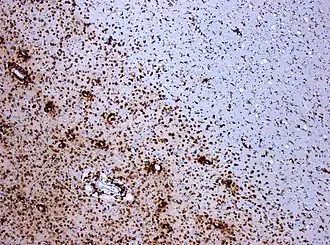

The hallmark of MS is the lesion, which appears mainly in the white matter and shows macrophage mediated demyelination, BBB breakdown, inflammation and axon transection.

Immune mediated attack

After the BBB breakdown, the immune-mediated attack against myelin happens. T cells, are a kind of lymphocyte that plays an important role in the body's defenses. The T cells recognize myelin as foreign and attack it, explaining why these cells are also called "autoreactive lymphocytes". Demyelination, further inflammation and axonal transection are the result.

The attack of myelin starts inflammatory processes, which triggers other immune cells and the release of soluble factors like cytokines and antibodies. Further breakdown of the blood–brain barrier, in turn cause a number of other damaging effects such as swelling, activation of macrophages, and more activation of cytokines and other destructive proteins.

Astrocytes can heal partially the lesion leaving a scar. These scars (sclerae) are the known plaques or lesions usually reported in MS. A repair process, called remyelination, takes place in early phases of the disease, but the oligodendrocytes are unable to completely rebuild the cell's myelin sheath. Repeated attacks lead to successively less effective remyelinations, until a scar-like plaque is built up around the damaged axons.

Demyelination patterns in standard MS

Four different damage patterns, known as Lassmann patterns,[58] have been identified by her team in the scars of the brain tissue in multiple sclerosis, and they are used sometimes as a basis for describing lesions in other demyelinating diseases.

- Pattern I

- The scar presents T-cells and macrophages around blood vessels, with preservation of oligodendrocytes, but no signs of complement system activation.[59]

- Pattern II

- The scar presents T-cells and macrophages around blood vessels, with preservation of oligodendrocytes, as before, but also signs of complement system activation can be found.[60] Though this pattern could be considered similar to damage seen in NMO, some authors report no AQP4 damage in pattern II lesions[61]

- Pattern III

- The scars are diffuse with inflammation, distal oligodendrogliopathy and microglial activation. There is also loss of myelin-associated glycoprotein (MAG). The scars do not surround the blood vessels, and in fact, a rim of preserved myelin appears around the vessels. There is evidence of partial remyelinization and oligodendrocyte apoptosis. For some researchers this pattern is an early stage of the evolution of the others.[62]

- Pattern IV

- The scar presents sharp borders and oligodendrocyte degeneration, with a rim of normal appearing white matter. There is a lack of oligodendrocytes in the center of the scar. There is no complement activation or MAG loss.